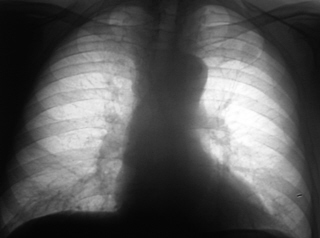

Проведено дообследование пациента на аппарате «Вироматик». Иллюстрация 4 – рентгенограмма в прямой стандартной проекции. Иллюстрации 5, 6 – фрагменты с увеличением изображения.

Иллюстрация 4. Фокусная тень средней интенсивности на уровне 1 межреберья слева с нечеткими, неровными контурами.

Иллюстрации 5, 6. Структура тени неоднородная, визуализируются мелкие просветления, что может свидетельствовать о мелкофокусном распаде, определяется дорожка к корню левого лёгкого.